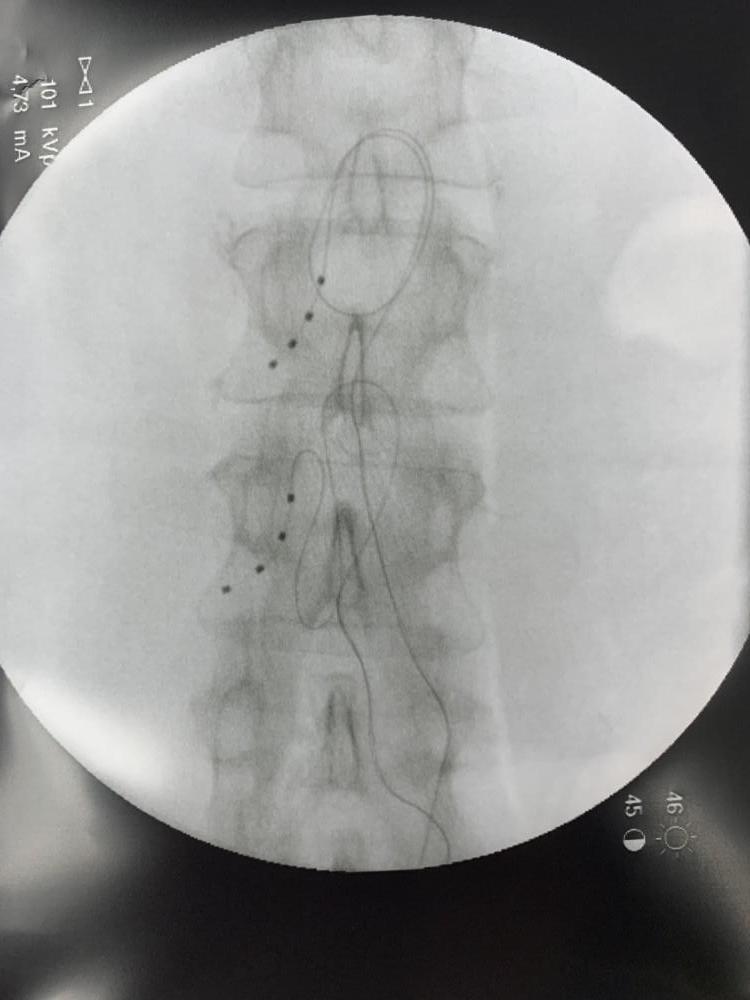

- Leads:Thin insulated wires that carry the electrical pulses from the generator to your dorsal root ganglia. These are placed in your body in the area of the DRG.

The implantation process for the dorsal root ganglion (DRG) stimulator is very similar to the implantation of a typical SCS. Like the typical SCS, the implantation of a DRG stimulator begins with a trial. After a 5-7 trial, you and your doctor will decide if the trial was successful based on your pain relief and then may decide to proceed with permanent implantation of the DRG generator device. Both the trial and the implantation are considered minimally-invasive treatments with short-recovery times and potentially immediate pain relief.